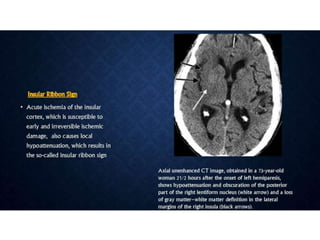

ACUTE STROKE IMAGINGPROTOCOL • When acute stroke patients present within 6 hours of the onset of symptoms - un-enhanced CT or with conventional/MR imaging. • Hemorrhage at unenhanced CT or >1/3 MCA territory - not treated with thrombolytic drugs. • Ischemia of < 1/3 MCA territory, those who present <3 hours after the onset of acute stroke - intravenous thrombolytic drugs • 3–6 hours after the onset of symptoms - CT angiography and CT perfusion imaging to assess the intracranial and neck vessels and detect any penumbra. • Intraarterial therapy is usually considered for patients in whom a penumbra is seen. • Patients in whom no penumbra is seen are not usually treated with thrombolytic drugs